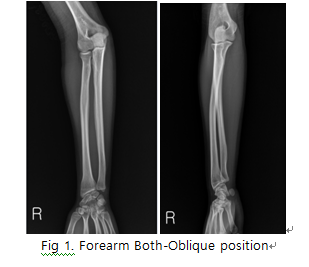

Forearm Both-Oblique

1. 목적

- ulna과 radius의 fracture 및 fracture에 따르는 elbow joint과 Articulations of hand의 변위 등의 병변 유무를 관찰한다.

2. 검사법

1) 환자자세

① 환자는 sitting으로 한다.

② medial oblique 촬영은 elbow joint의 전면이 카세트면에 40~45도 되게 pronation시킨다.

③

lateral oblique 촬영은 elbow joint의 전후면 자세에서 후면이 카세트면에서 40도 되게 자세를 유지한다.

2) 호흡법 : 편안한 상태로 시행한다.

5) 촬영 거리 : SID는 110 cm으로 촬영한다.

6) 영상 결과

① Articulations of hand과 elbow joint 포함

② radial head, neck of radius, radial tuberosity 의 ulna Proximal part 위에 일부 겹침

③ humerus epicondyle의 확대유무 확인